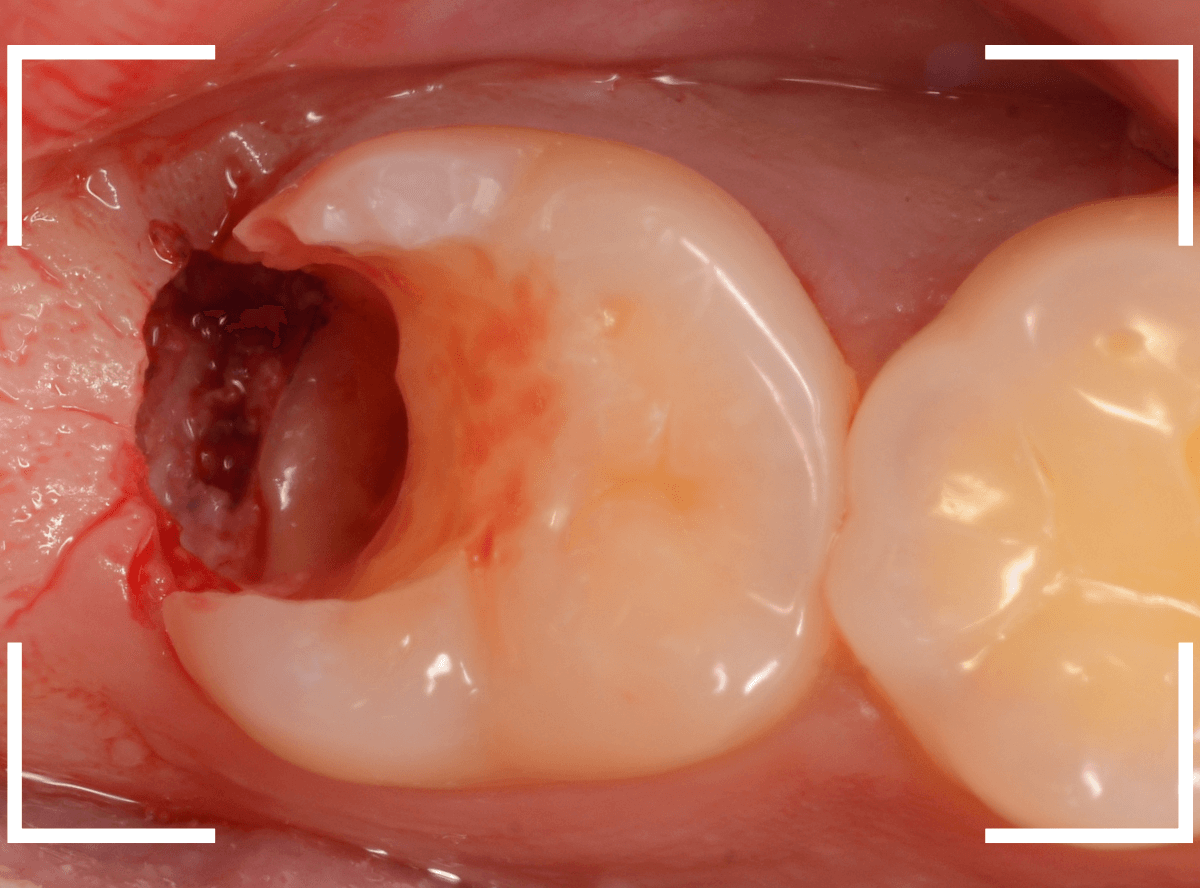

まず、つめものを外します。

歯肉を処置しながら、虫歯を除去します。

虫歯の全て除去後、止血したところです。

かなり深いところまで虫歯が進行していましたが、なんとかぎりぎり抜歯せずに、土台を作って噛み合わせを回復できそうです。

神経を取った歯は、虫歯がいくら進行しても痛みにならず、最悪、抜歯一直線になってしまいます。